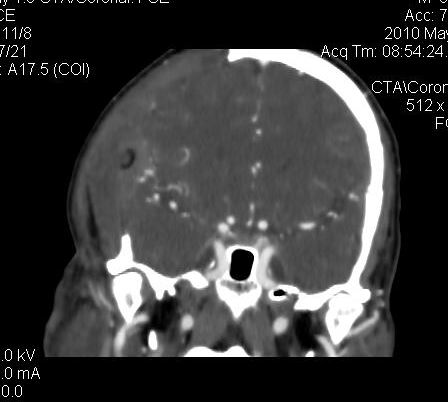

男.60岁,渐进性意识不清,ct检查双侧额颞顶部硬膜下血肿,开颅术后行脑血管cta,大脑中动脉起始部见一瘤状血管扩张。请各位老师留下宝贵意见

太常见了,报动脉瘤就可以

符合动脉瘤表现。

符合动脉瘤表现。

动脉瘤。

颅内动脉瘤。

后重建做得不是很好看,要将维蒂斯环充分显示,最好在增加一个mip。这样不好定位。

小动脉瘤

典型

符合动脉瘤的表现

动脉瘤

符合动脉瘤表现。

小动脉瘤

典型